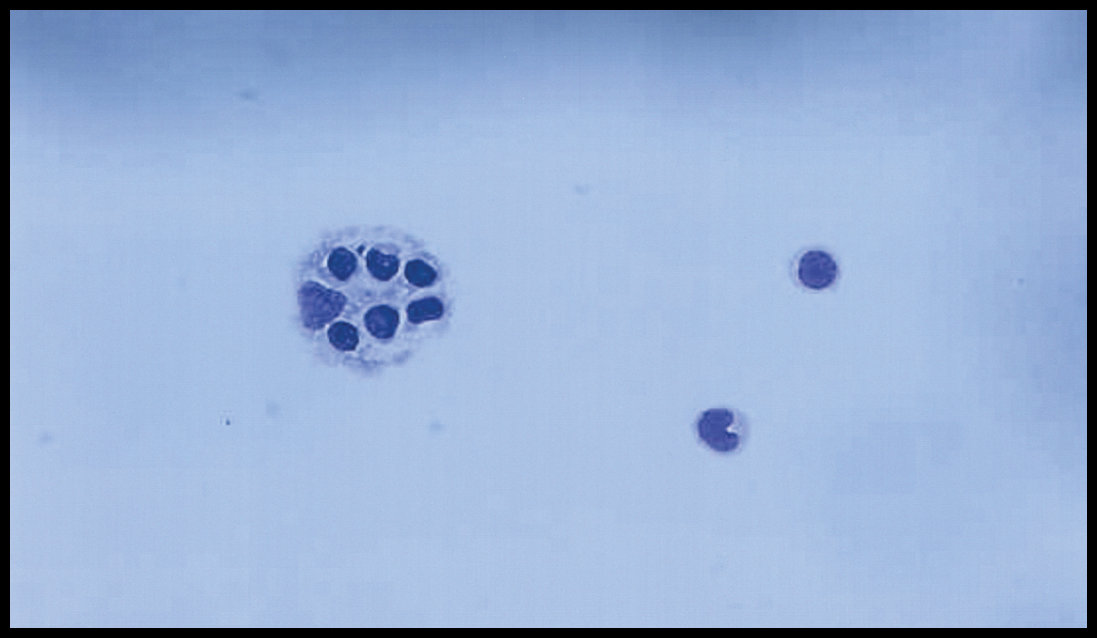

◆ 组织病理学

骨髓中巨噬细胞吞噬现象(噬血现象)

骨髓吞噬细胞